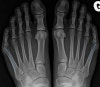

소지내반증의 영상 검사

체중부하 상태에서 AP view를 찍으면 다섯째 중족골의 몸쪽은 안쪽으로, 다섯째 중족골간(intermetatarsal bone)는 가쪽으로 편위 그리고/또는 중족골두 가쪽의 돌출 소견을 보입니다.

관절 자체는 대개 정상입니다.

X-ray : 소지내반증(Bunionette, Tailer’s bunion)